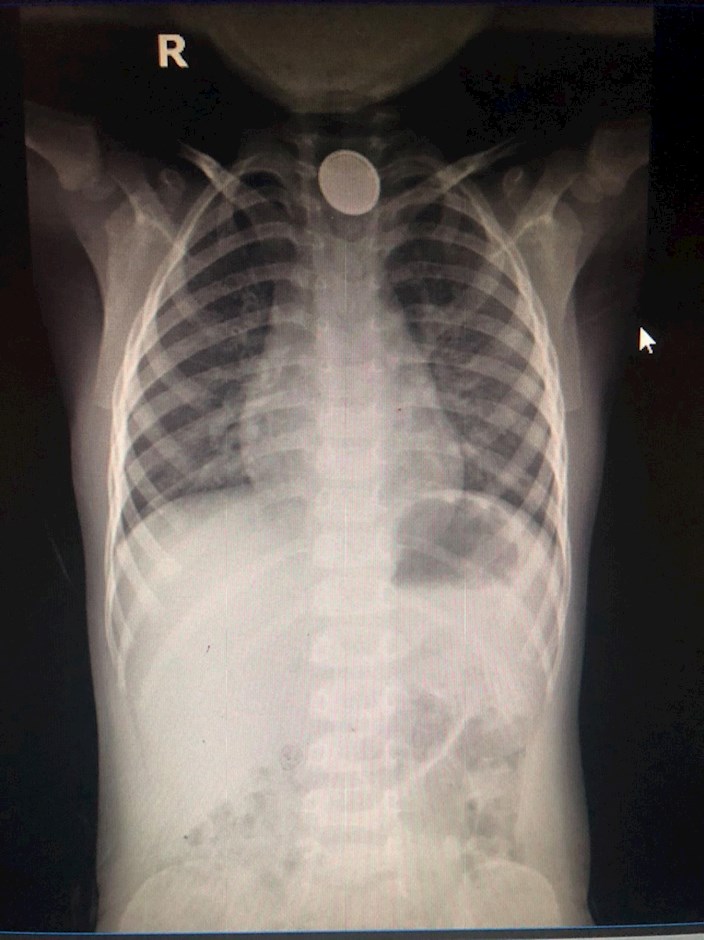

Hình ảnh dị vật nằm trong thực quản bệnh nhi.

Theo đó, tối 6/1, anh H. nghe con than mệt, đau ở cổ họng, ăn vào nôn ói và ho sặc sụa nên gia đình lập tức đưa bé đến Phòng khám Nhi của Bệnh viện quận Thủ Đức. Qua kiểm tra lâm sàng, nghi ngờ bé T. nuốt phải dị vật, bác sĩ nhanh chóng cho bé chụp X-Quang. Hình ảnh chụp cho thấy chỗ 1/3 thực quản trên của bé có dị vật kim loại hình tròn. Bé được đưa vào phòng mổ để gây mê, nội soi gắp dị vật khẩn.